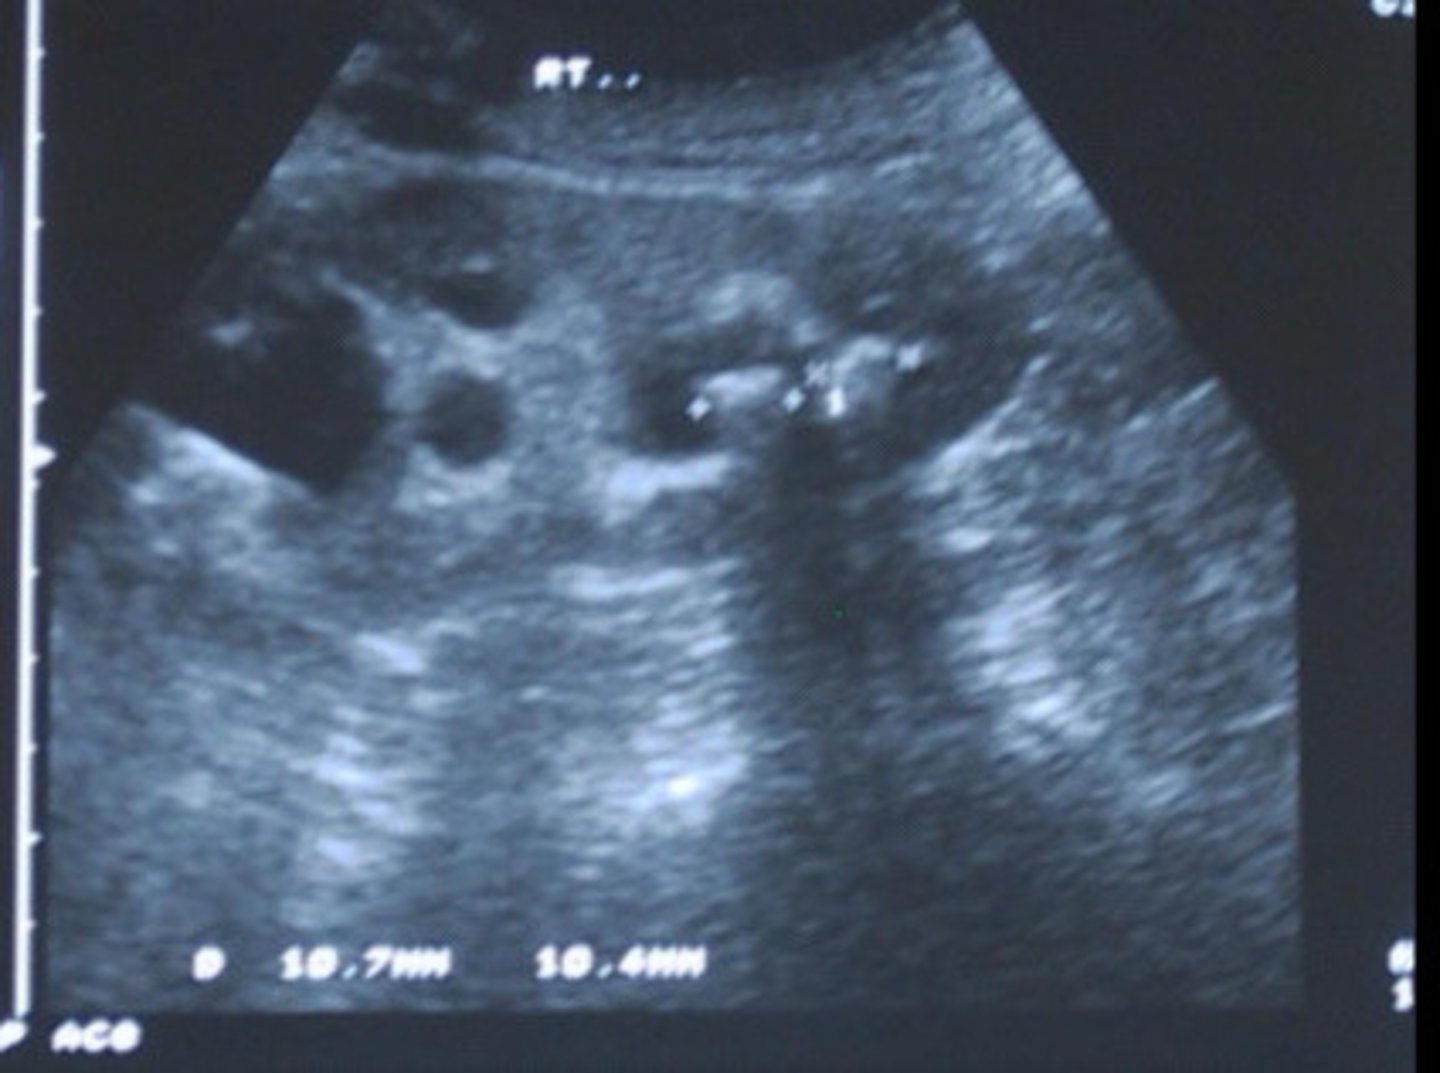

Stone difficult to identify in the sinus region

What does this image show